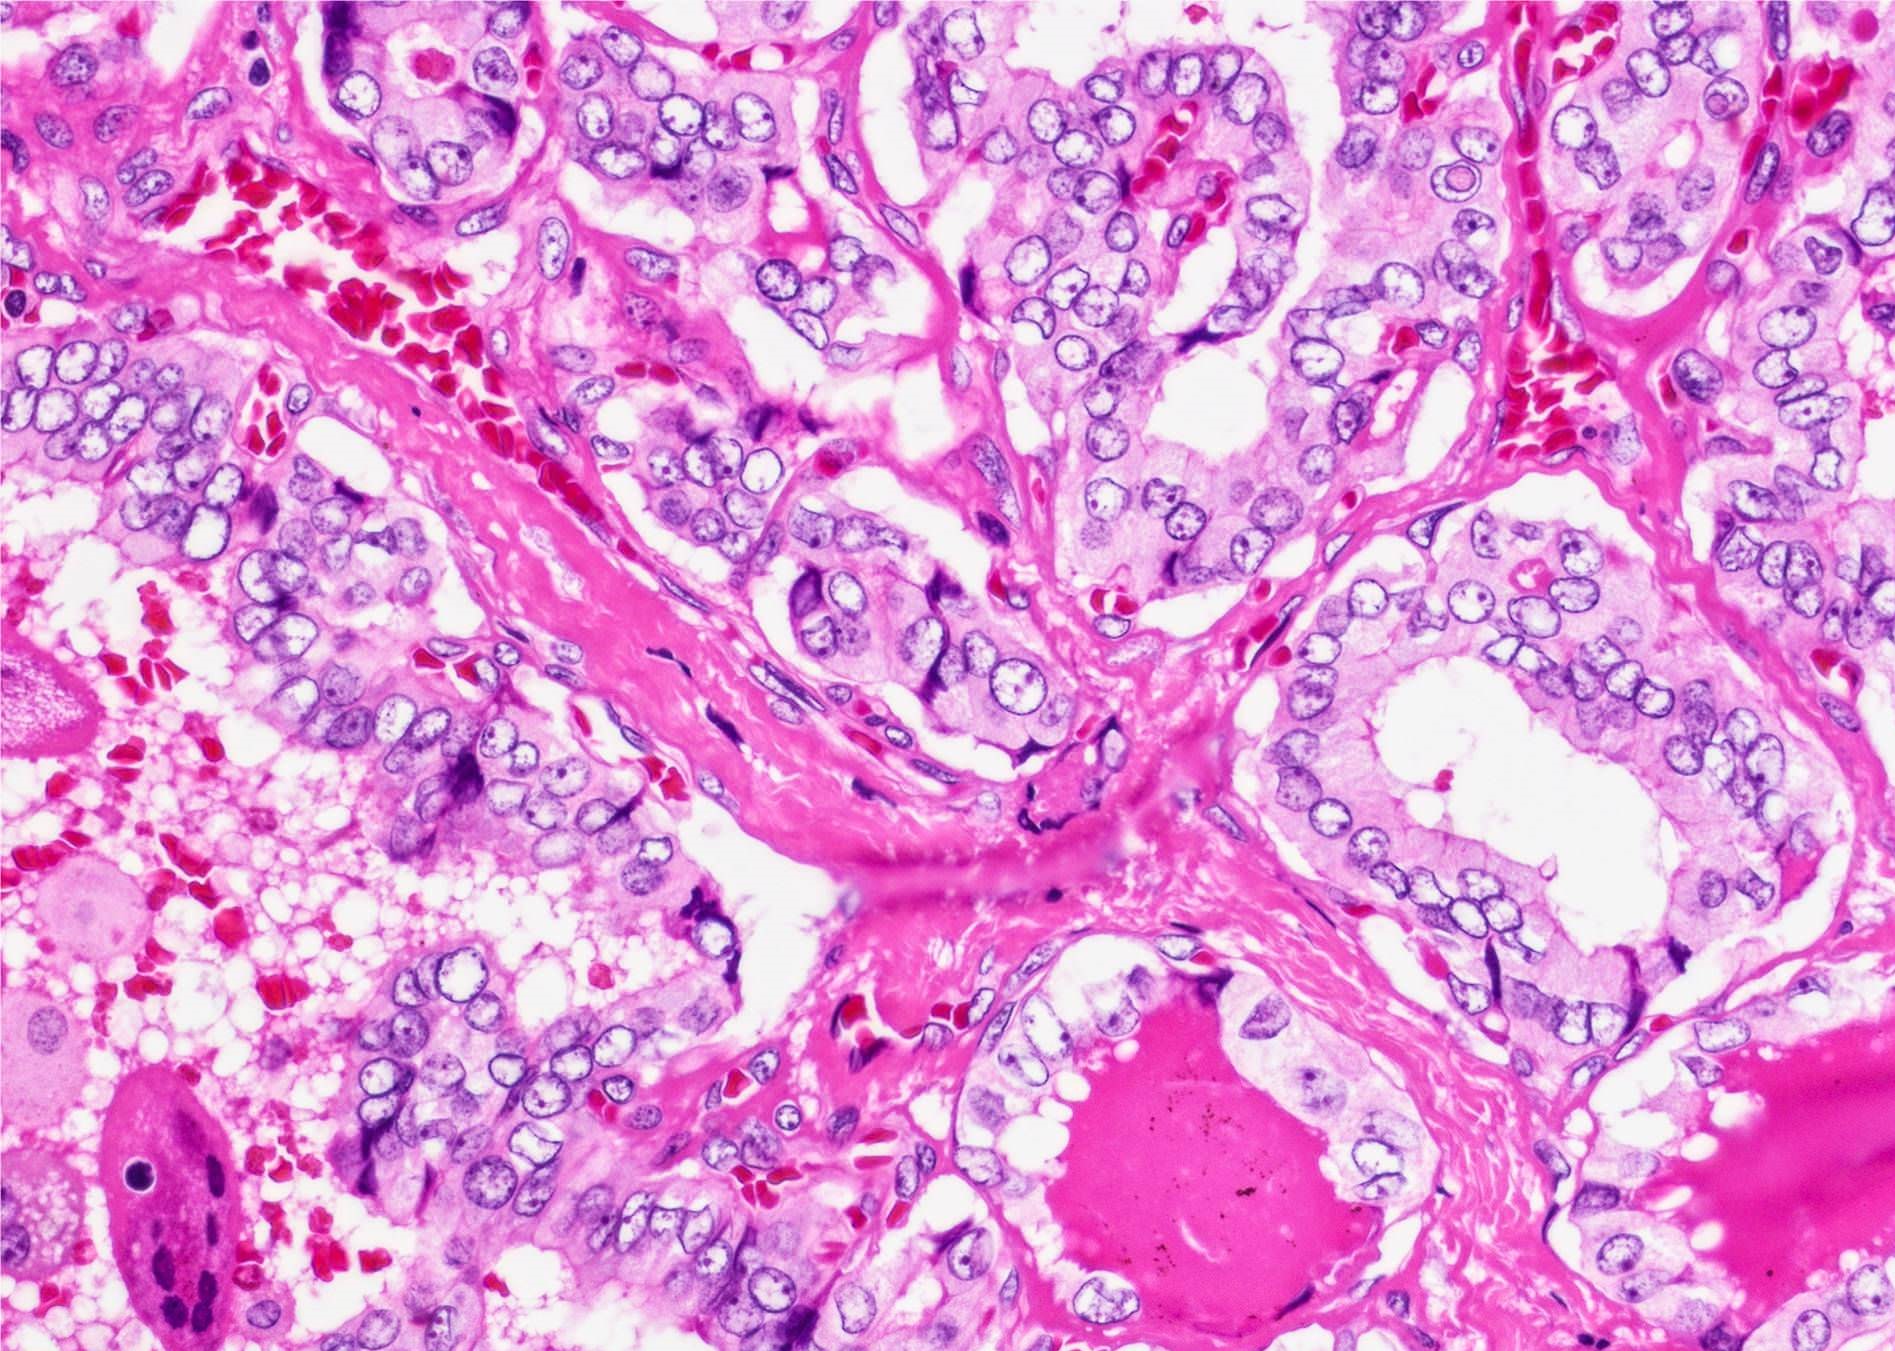

Microscopic (histologic) description

- Nuclear features of papillary thyroid carcinoma should be seen multifocally (at least 2 foci) or diffusely within the tumor; such features include nuclear enlargement, nuclear overlapping, chromatin clearing, nuclear membrane irregularity and nuclear grooves (J Clin Endocrinol Metab 2017;102:15)

- Architecture: exclusively or nearly exclusively follicular

- Infiltrative follicular variant shows infiltrative or multinodular growth

- Sprinkling sign refers to the phenomenon that neoplastic follicles are seen scattered within the background of normal follicles

- "Bubble gum colloid", i.e. dense homogenous hypereosinophilic colloid, may be seen in the lumen of neoplastic follicles; scalloping of colloid may be seen

Microscopic (histologic) images